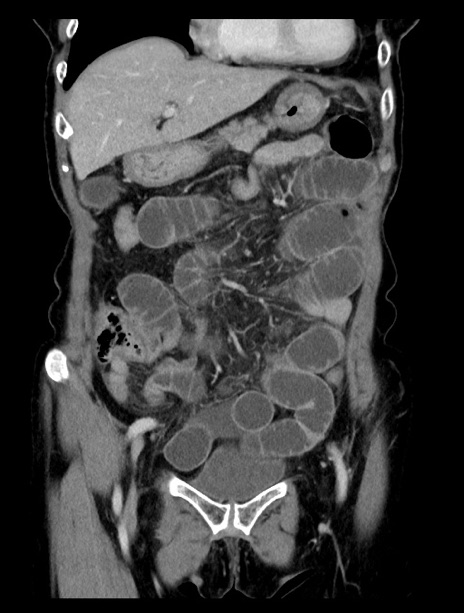

症例23(冠状断像)

【症例】70歳代女性

【主訴】下腹部痛・嘔吐

【現病歴】2日前より腹痛あり。昨日嘔吐あり。症状改善しないため来院。

【既往歴】胃GISTに対して胃部分切除後。

【身体所見】BT 37.1℃、BP 128/77mmHg、腹部:平坦・軟、下腹部に圧痛あり。

【データ】WBC 10200、CRP 0.31